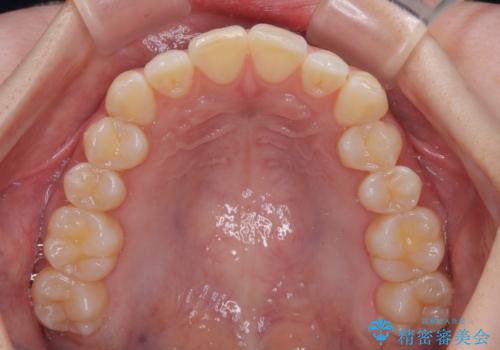

- 上下前歯の重なりを気にして来院された患者様です。

安価なインビザラインパッケージを用いての治療を希望されており、デコボコの程度が中等度であったため、インビザライン・モデレートを用いて矯正治療を行うこととしました。

インビザライン・モデレートは、製作できるアライナーの枚数に制限があるため、移動可能な量に限りがあるものの、インビザライン・ライトよりも枚数が多いため、幅広い症例に対応可能です。